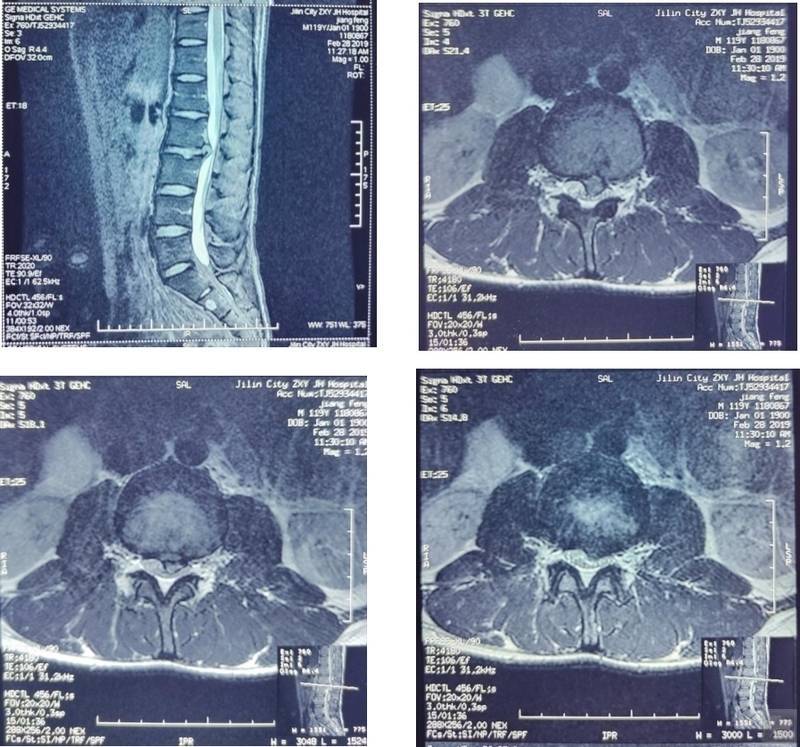

患者主诉“腰痛伴左下肢放射痛2天”。患者于2天前患者在家抬举重物时腰部出现弹响,而后出现腰痛伴左下肢放射痛,卧床休息后未改善,于本院查腰椎MRI示(如图): L2~L3椎间盘向左后方脱出,左侧神经根受压。就诊时症见:患者腰骶部疼痛,弯腰活动受限,左下肢放射痛,疼痛区集中在大腿前侧,纳眠可,二便调,舌淡红,苔白,脉细。

随访:该患者于2022年10月25日在我院体检,腰椎MRI(如图)示: L2~L3椎间盘膨出。患者症状消失。